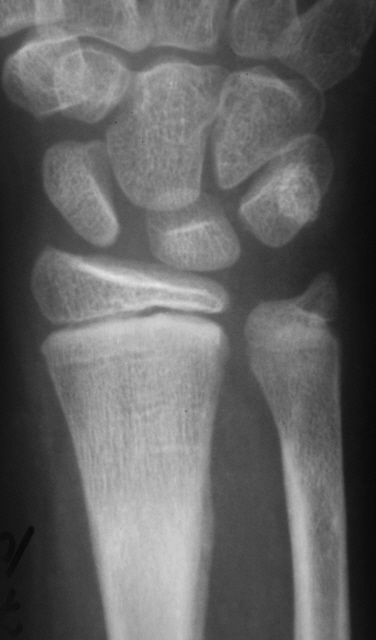

Пациент направлен в рентгеновский кабинет врачом хирургом, по поводу болей в дистальной трети предплечья. Пациент и его родители утверждают, что травмы не было.

Снимки с более высокой степенью разрешения.

Определяются локальные оссифицированные периостальные наслоения в н/3 диафиза лучевой кости, что-то наподобие дефекта со склеротическим контуром по передней поверхности кости. У меня три варианта: 1 - консолидированный перелом лучевой кости; 2 - патологическая перестройка (читала у Рейнберга, может встречаться в лучевых и локтевых костях, выглядит как консолидированный перелом); 3 - первично-хр. остеомиелит.

Больше похоже на срастающийся перелом.

Но т равмы не было. Чем может быть вызвана "одностороняя реакция надкостницы"?

Меня тоже смущает, и очень. Отправляйте к детским онкологам, пусть они контролируют. Основание: диафиз лучевой кости бульбообразно расширен ("поддут"), структура кости уплотнена муфтообразно/"пояском", менее выраженные, чем по переднему стенке кости, но аналогичные изменения отмечаются и по задней стенке диафиза, плюс периостальная реакция в прямой проекции.